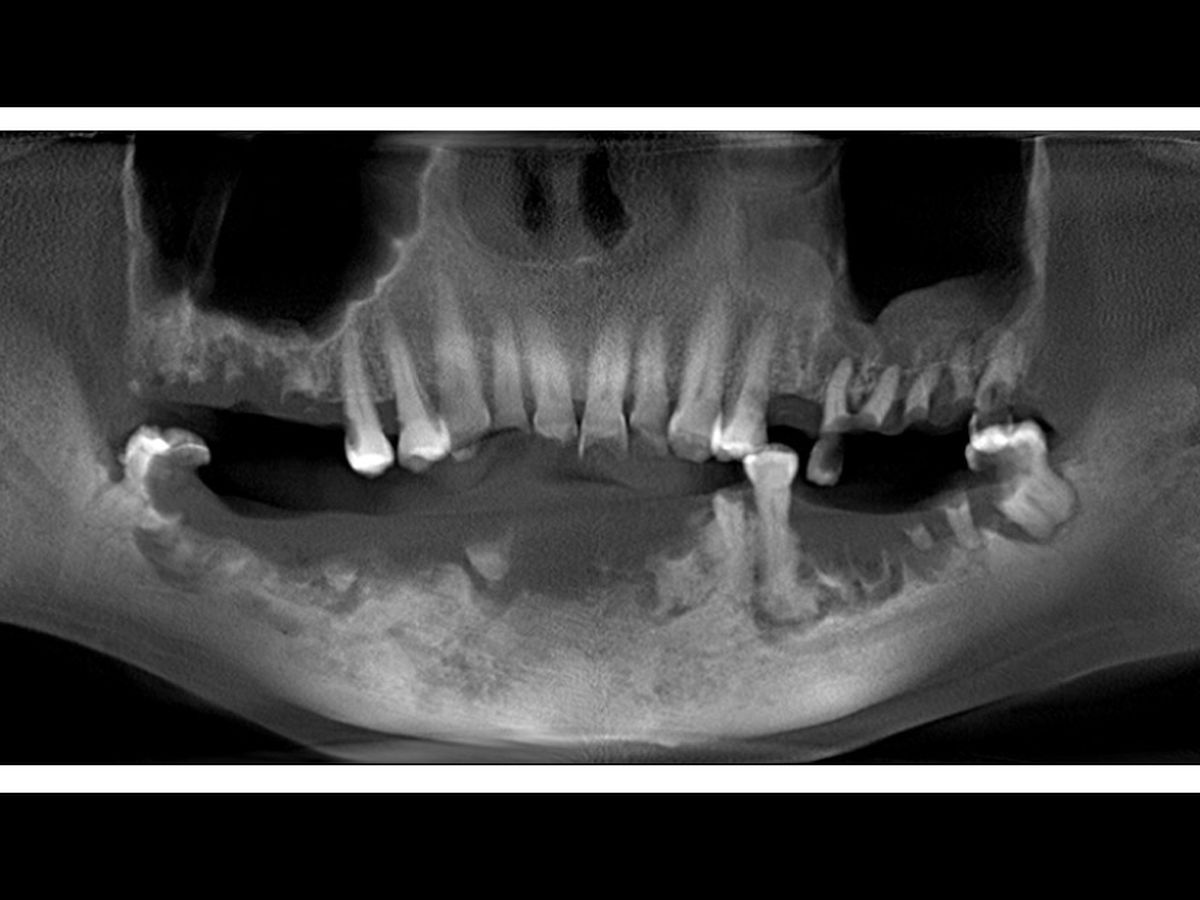

Hello! My name is Rose Maldonado. I'm 47 years old, and I'm a cancer survivor. When I just turned 26, I had cancer on my tongue. They removed almost the entire back of the right side and also extracted 47 lymph nodes. Then I received 30 sessions of radiation in the jaw and neck. I was recently diagnosed with Jaw Radiation Necrosis (JRN), a condition caused by radiation. It has destroyed all the cells and tissues of my jaw, blood does not circulate, and it has progressively expelled part of the lower teeth, It's hard for me to eat only puree and liquid, which has made me lose weight drastically, causing multiple facial inflammations, clotting, bleeding, extreme pain, fever, and severe infections. These infections put my life at great risk since they could expand to the brain, which could be fatal.